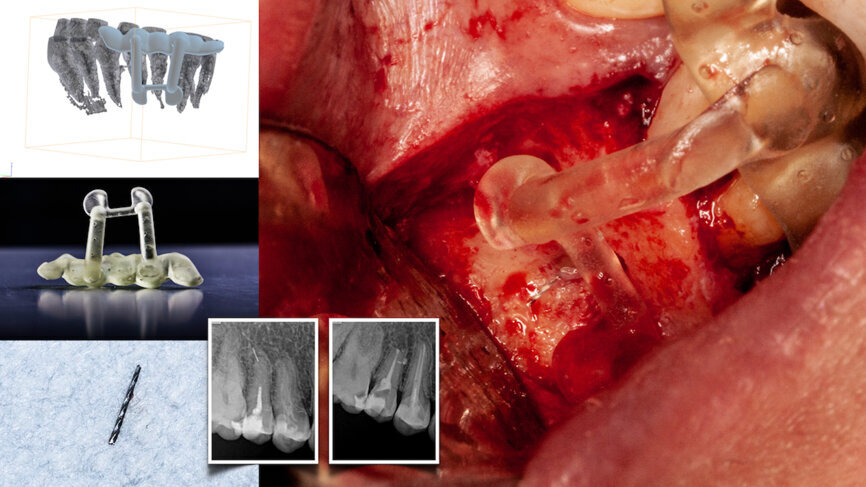

Fig. 1a: Static navigation stent used for endodontic access cavity preparations. The pre-planned stent does not allow for reorientation of the drill during the preparation. This can be consequential in accessing calcified, sclerosed canals. (Courtesy of Dr Paula Villa)

Fig. 1b: Three-dimensional stent printed for static navigation guidance to facilitate removal of an instrument in the periapex. Stents are cumbersome, bulky and restrictive in posterior regions. Once planned, the osteotomy path cannot be altered. (Courtesy of Dr Hugo Sousa Dias)

The advent of cone beam computed tomography (CBCT—DICOM files) and 3D printing has transformed pretreatment planning. DICOM files are converted into stereolithic files, which are used to create static navigation stents (CAD/CAM-fabricated). The stents direct the access cavity preparation and microsurgical orientation, thus avoiding removal of unnecessary tooth and bone structure (Figs. 1a & b).